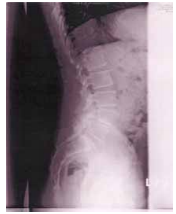

57 64 歲許先生罹患腰痛已經 8 年,其 X 光檢查如右圖, 則下列何種手法應該慎用?

(A)拿捏法 (B)滾法 (C)按壓法 (D)揉法